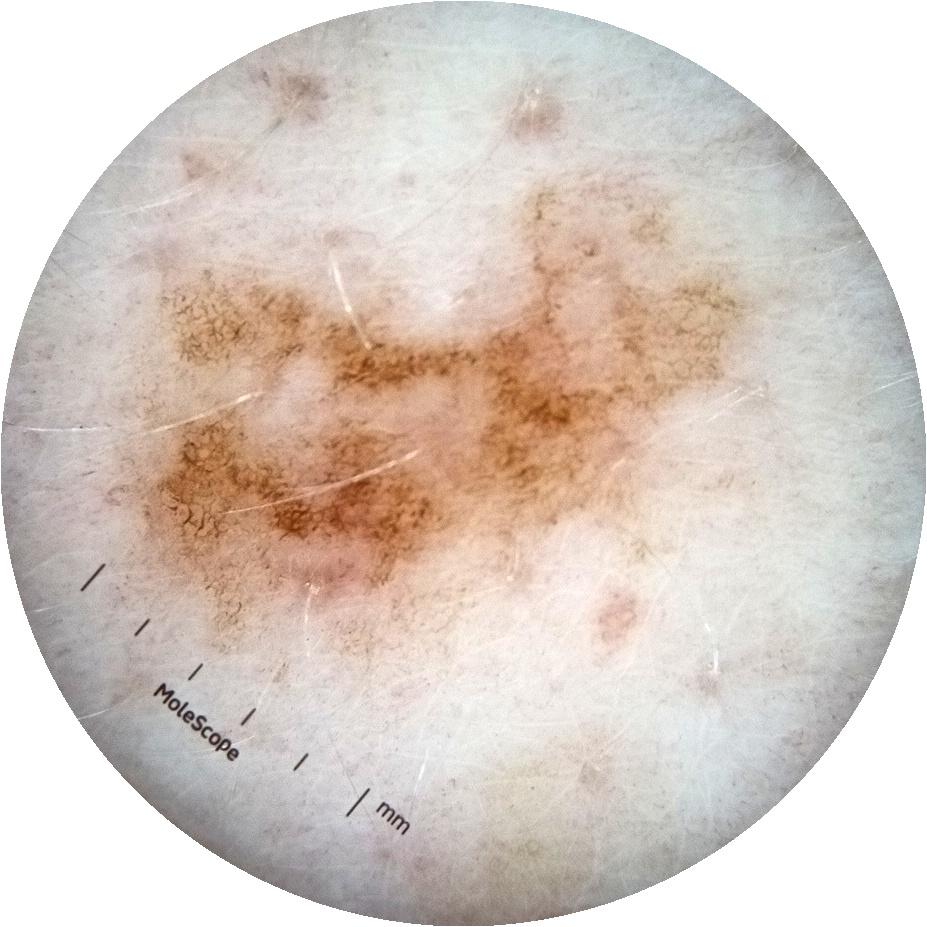

ISIC_3754278

acquisition_day 135

age_approx 65

anatom_site_1 Upper extremity

diagnosis_1 Benign

diagnosis_confirm_type single image expert consensus

fitzpatrick_skin_type I

image_type dermoscopic